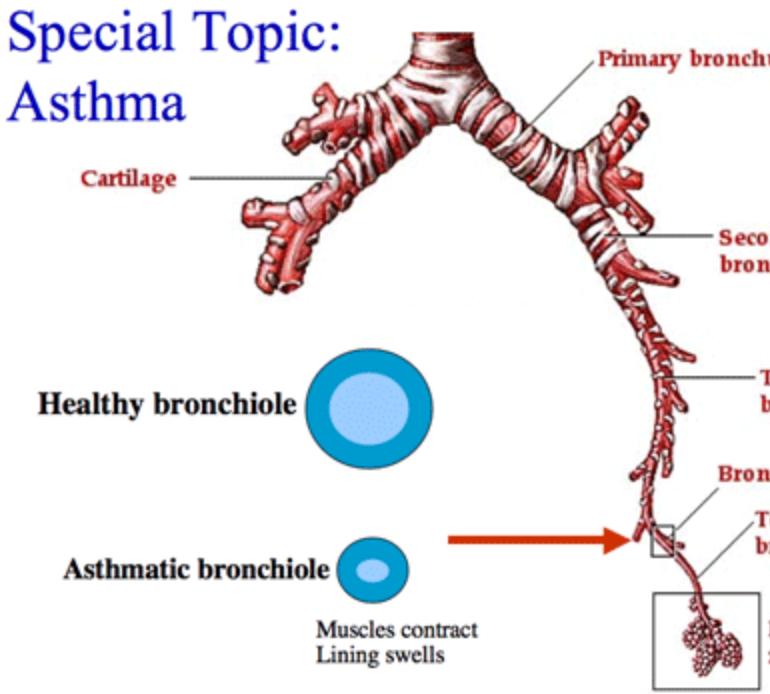

Bronchiole

Terminal bronchiole

Respiratory bronchiole